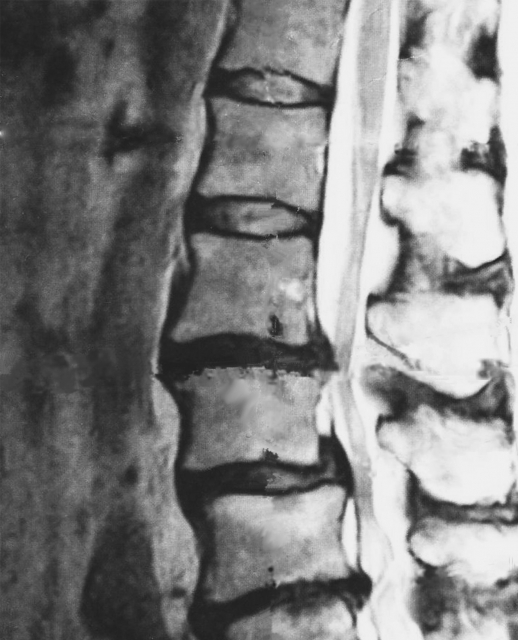

MRI画像

この研究の最も衝撃的な点は、「腰に全く痛みを感じていない健康な人」を3,000人以上集めてMRI検査を行ったことです。その結果、以下のような驚くべきデータが得られました。

30代の約50%に、椎間板(背骨のクッション)の変性が見られた。

50代では約80%の人に、同じような異常が見つかった。

80代に至っては、なんと96%の人に異常が見られた。

つまり、痛みがないにもかかわらず、画像の上では「ヘルニア」や「骨の変形」が見つかることが、現代人にとってはむしろ「当たり前のこと」だと証明されたのです。

論文が示したのは、MRIに映る変形やヘルニアの多くは、痛みとは無関係な「体の中のシワ」のようなものだということです。たとえ画像で「異常」と診断されても、それが今の痛みの直接の犯人である確率は、私たちが思っているよりもずっと低いのです。